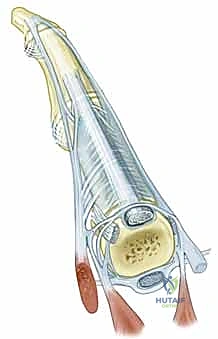

قبل الخوض في التفاصيل التقنية للإجراء الجراحي، من الضروري والمحوري أن نفهم البنية التشريحية المعقدة لمفصل MCP. هذا المفصل هو الرابط الحيوي بين عظام راحة اليد (الأمشاط - Metacarpals) وعظام الأصابع الأولى (السلاميات القريبة - Proximal Phalanges). يُصنف هذا المفصل على أنه مفصل لقمي (Condyloid Joint)، مما يعني أنه يسمح بحركات متعددة في مستويات مختلفة: الثني (Flexion)، البسط (Extension)، الانحراف الزندي (Ulnar Deviation)، الانحراف الكعبري (Radial Deviation)، بالإضافة إلى الحركة الدائرية المحدودة (Circumduction).

- الصفيحة الراحية (Volar Plate): هي بنية قوية جداً، ليفية غضروفية في جزئها البعيد (حيث تتصل بالسلامية)، وغشائية مرنة في جزئها القريب. تعمل هذه الصفيحة كحاجز ميكانيكي حاسم، يحد من فرط بسط مفصل MCP ويمنع خلع المفصل للخلف. كما يرتبط بها غمد الوتر القابض (البكرة A-1) بإحكام.

- وتر الباسطة الرقمية المشتركة (Extensor Digitorum Communis - EDC): هو اللاعب المركزي والنجم في إجراء اليوم الجراحي. يتم الاحتفاظ بهذا الوتر في المنتصف تماماً فوق قمة مفصل MCP بواسطة هياكل تُعرف بـ الأربطة السهمية (Sagittal Bands).

- الأربطة السهمية: هي ألياف مستعرضة قوية تنشأ من غطاء الباسطة (Extensor Hood) وتتصل من الناحية الراحية بالصفيحة الراحية والرباط بين الأمشاط المستعرض، لتشكل آلية تشبه "الحبال" أو "المقلاع" (Sling mechanism) تحافظ على الوتر في مكانه. يُعتبر الرباط السهمي الزندي عموماً أقوى وأكثر كثافة من نظيره الكعبري، وهو عامل بيوميكانيكي يساهم في سهولة انزلاق الوتر نحو الجهة الزندية (Ulnar Subluxation) عندما يضعف الرباط الكعبري بسبب المرض.

- ملاحظة هامة: من المثير للاهتمام أنه لا يوجد عادةً إدخال مباشر (Insertion) لوتر الباسطة الرئيسي في السلامية القريبة؛ بل يتم تحقيق بسط المفصل من خلال آلية الحبال (Sagittal bands) التي تسحب السلامية القريبة عند انقباض العضلة.

- العضلات الداخلية (Intrinsic Muscles): تشمل العضلات الخراطينية (Lumbricals) والعضلات بين العظام (Interossei). تلعب هذه العضلات دوراً حاسماً في ثني مفصل MCP وبسط مفاصل الأصابع الأخرى (PIP و DIP). في مرض الروماتويد، غالباً ما تتقلص العضلات الداخلية الزندية، مما يسحب الأصابع بقوة نحو الانحراف الزندي.

- الانزلاق الزندي للوتر الباسط (Ulnar Subluxation of EDC): بمجرد ضعف الرباط السهمي الكعبري، ينزلق وتر الباسطة (EDC) من أعلى قمة المفصل نحو الوادي الزندي بين الأمشاط. عندما يحدث هذا، يفقد الوتر قدرته على بسط الإصبع بفعالية، وبدلاً من ذلك، تصبح قوة سحبه مساهمة في زيادة الانحراف الزندي للأصابع.